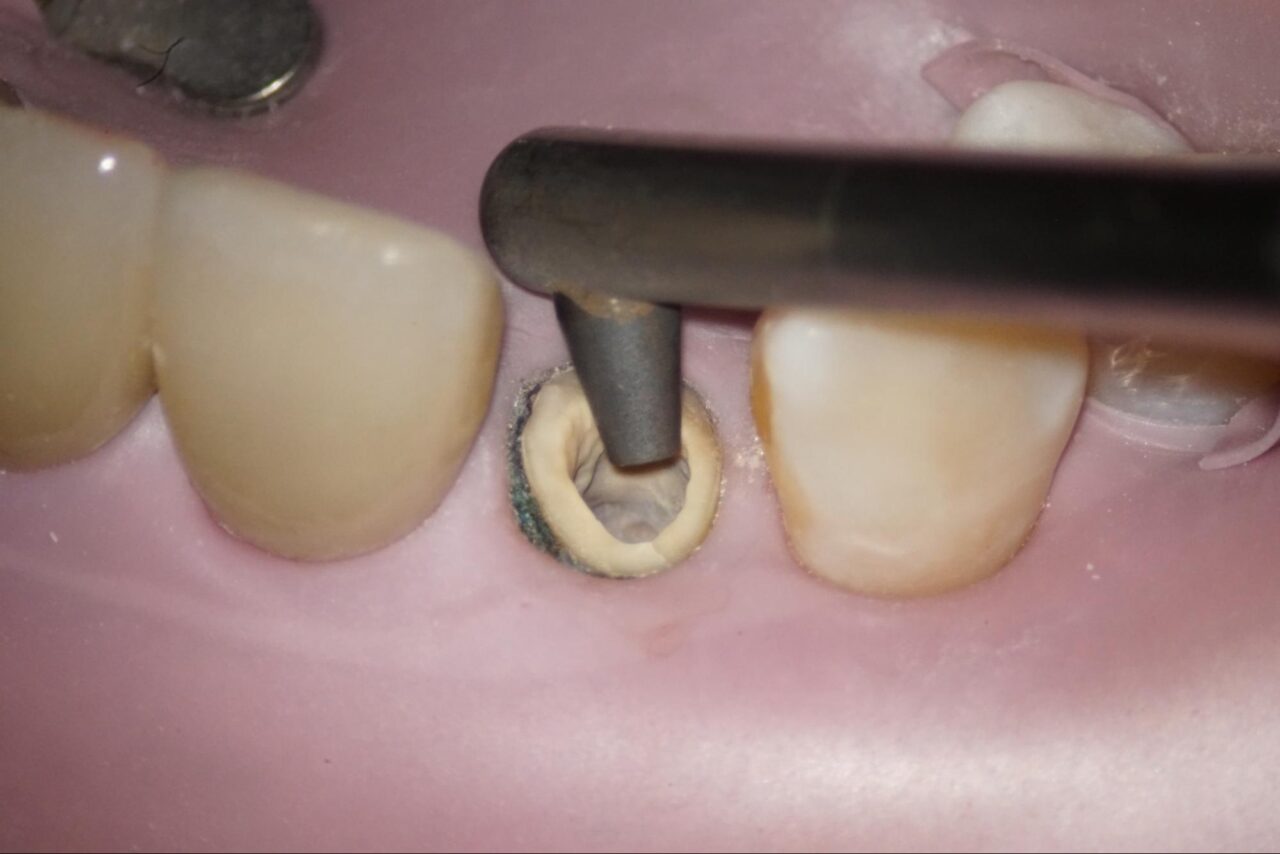

他院で歯根破折を疑われて、当院に来院されました。麻酔後にラバーダム防湿を行い、その後修復物を外します。

可能な限り健全歯質を削らないように細心の注意をはらって以前の修復物を外します。

ファイバーコアを除去していきます。

余分な健全歯質をできるだけ削らないように拡大視野の中で丁寧に人工物や感染歯質を削っていきます。

感染部がグリーンに染まるカリエスディテクターを用いながら削っていくと頰側にクラックが入っている事が確認できます。